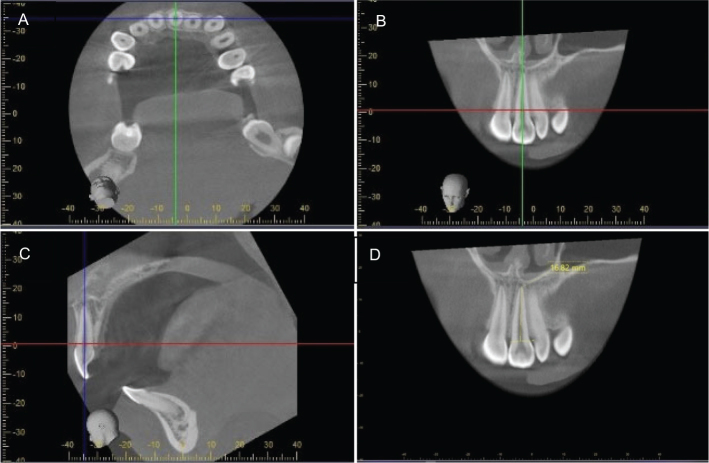

Objectives: To assess inter- and intrarater reliability and agreement for measurements of root lengths using multiplanar reconstruction (MPR) in cone beam computed tomography (CBCT) examinations.Furthermore, to determine whether using MPR from different CBCT machines was a reliable and reproducible method for assessment of root length during orthodontic treatment of adolescents.

Materials and methods: A total of 40 CBCT examinations obtained before, during and after orthodontic treatment of 14 adolescents, with fixed appliances from a multicentre randomised controlled trial, were used. All roots from the incisors to the first molars were measured by two independent raters and in accordance with a protocol preceded by a multi-step calibration. Reliability was assessed by intra class correlation (ICC). Agreement was assessed by measurement error according to the Dahlberg formula and Bland-Altman plot.